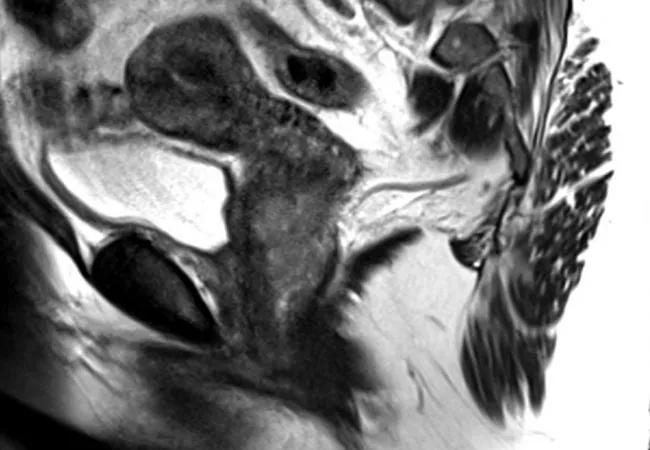

A 58-year-old woman presented to Cleveland Clinic with post-menopausal bleeding. Gynecologic oncologist Peter Rose, MD, ordered an MRI which showed an enhanced cervical mass. Further testing uncovered small bilateral cervical lymph nodes with mild FDG uptake SUV of 2.7, concerning for metastases.

Feature image: MRI of the pelvis, sagittal section of the uterus and cervix demonstrating cervical tumor. Republished with permission from Elsevier.